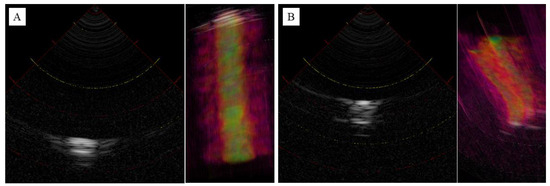

3.1. Probe Sound Field Property Measurement

3.2. Observation of the Agar Phantom